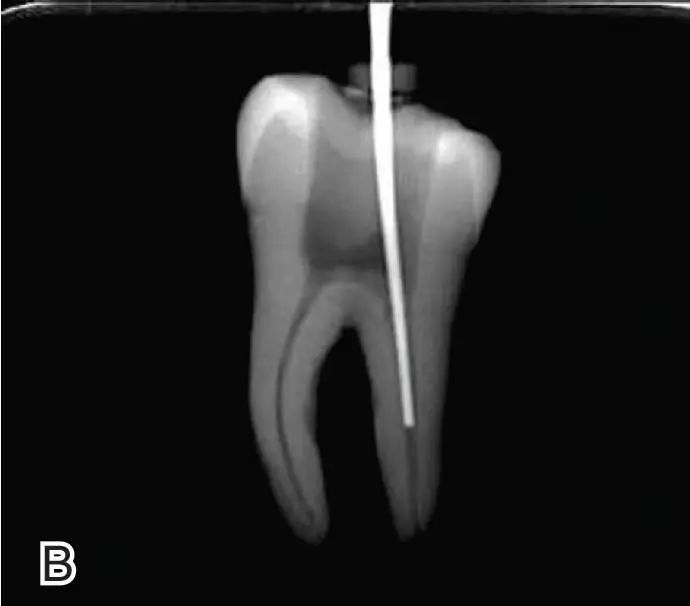

试尖

选择非标准牙胶尖(如0.04、0.06 锥度牙胶尖)作为主尖,型号一般与根管预备最大号的器械型号一致,能到达距根尖0.5~1 mm 处,主尖尖段与根管壁紧密接触。拍试尖X 线片进行确认。